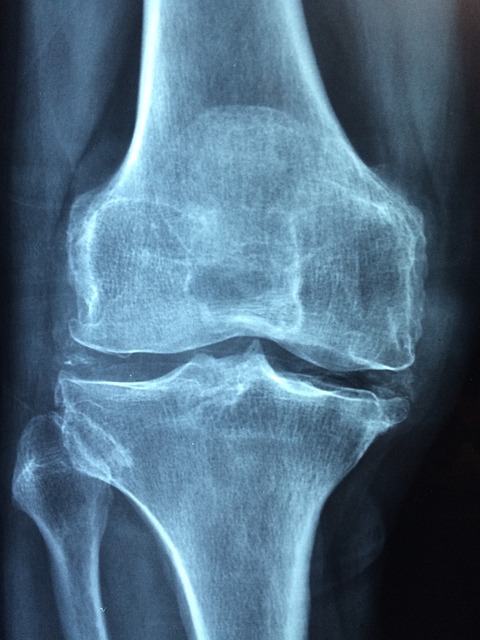

무릎 관절은 우리 몸에서 가장 많은 부담을 받는 부위 중 하나입니다. 걷기, 뛰기, 앉았다 일어나기 등 일상적인 활동에서 지속적으로 사용되기 때문에 무릎 건강이 악화되면 생활의 질이 크게 떨어질 수 있습니다.

무릎 관절 건강을 유지하기 위해서는 올바른 식습관, 적절한 영양제 섭취, 그리고 관절을 보호하는 운동이 필수적입니다. 이번 글에서는 무릎 관절에 좋은 건강식품, 영양제, 그리고 효과적인 운동법까지 알아보겠습니다.